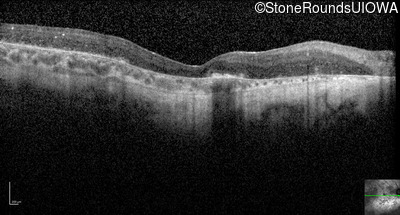

Optical Coherence Tomography - Right - No Light Perception

Exemplar / OCT Stack

Optical Coherence Tomography - Left - Light Perception